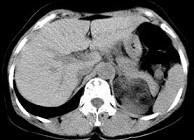

问题 男性,28岁,左腰背酸胀5个月,CT检查如图所示,应诊断为()

选项 A.左肾上腺髓样脂肪瘤 B.左肾上腺错构瘤 C.左肾上腺嗜铬细胞瘤 D.左肾上腺腺瘤 E.左肾上腺转移瘤

答案 B